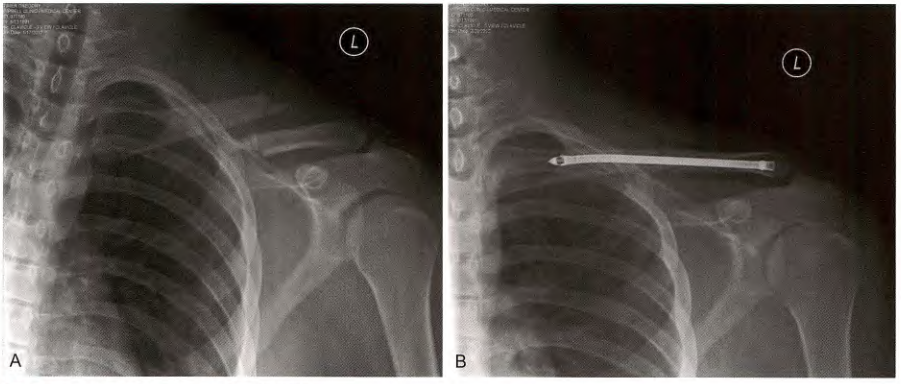

A. 锁骨骨折, B髓内钉治疗

使用带尾帽远端有螺纹的髓内钉固定(Rockwood 锁骨钉)